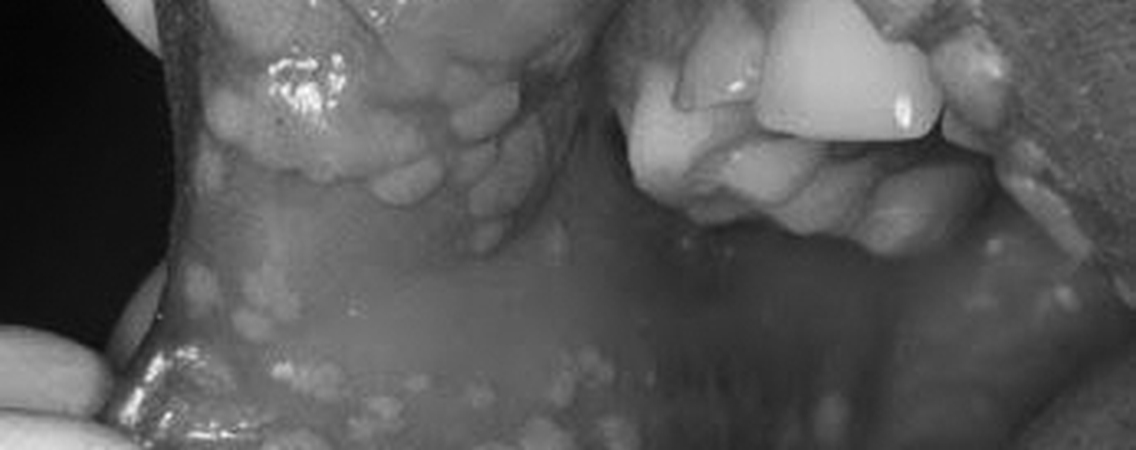

New evidence has linked the presence of HPV in an oral mucosal infection to the increase risk of oral and oral pharyngeal cancer. It has been a challenge in the past to identify those individuals with these risk factors until now. In this highly interactive program participants will learn to conduct an Oral Abnormality Screening TM Exam and optimize verbal skills to educate the patient about self-examination techniques without invoking the fear of the threat of cancer. We will review the importance of consistently conducting an effective oral abnormality visual and tactile “lump, bump & bulge” screening exam each time all patients are in our care.We will discuss adjunctive oral cancer screening technologies as well as review why oral systemic health and wellness are key to oxidizing viral infections. Finally, we will have a check list of what products we can safely recommend to patients that are going through cancer therapy and why our position is so valuable to them.